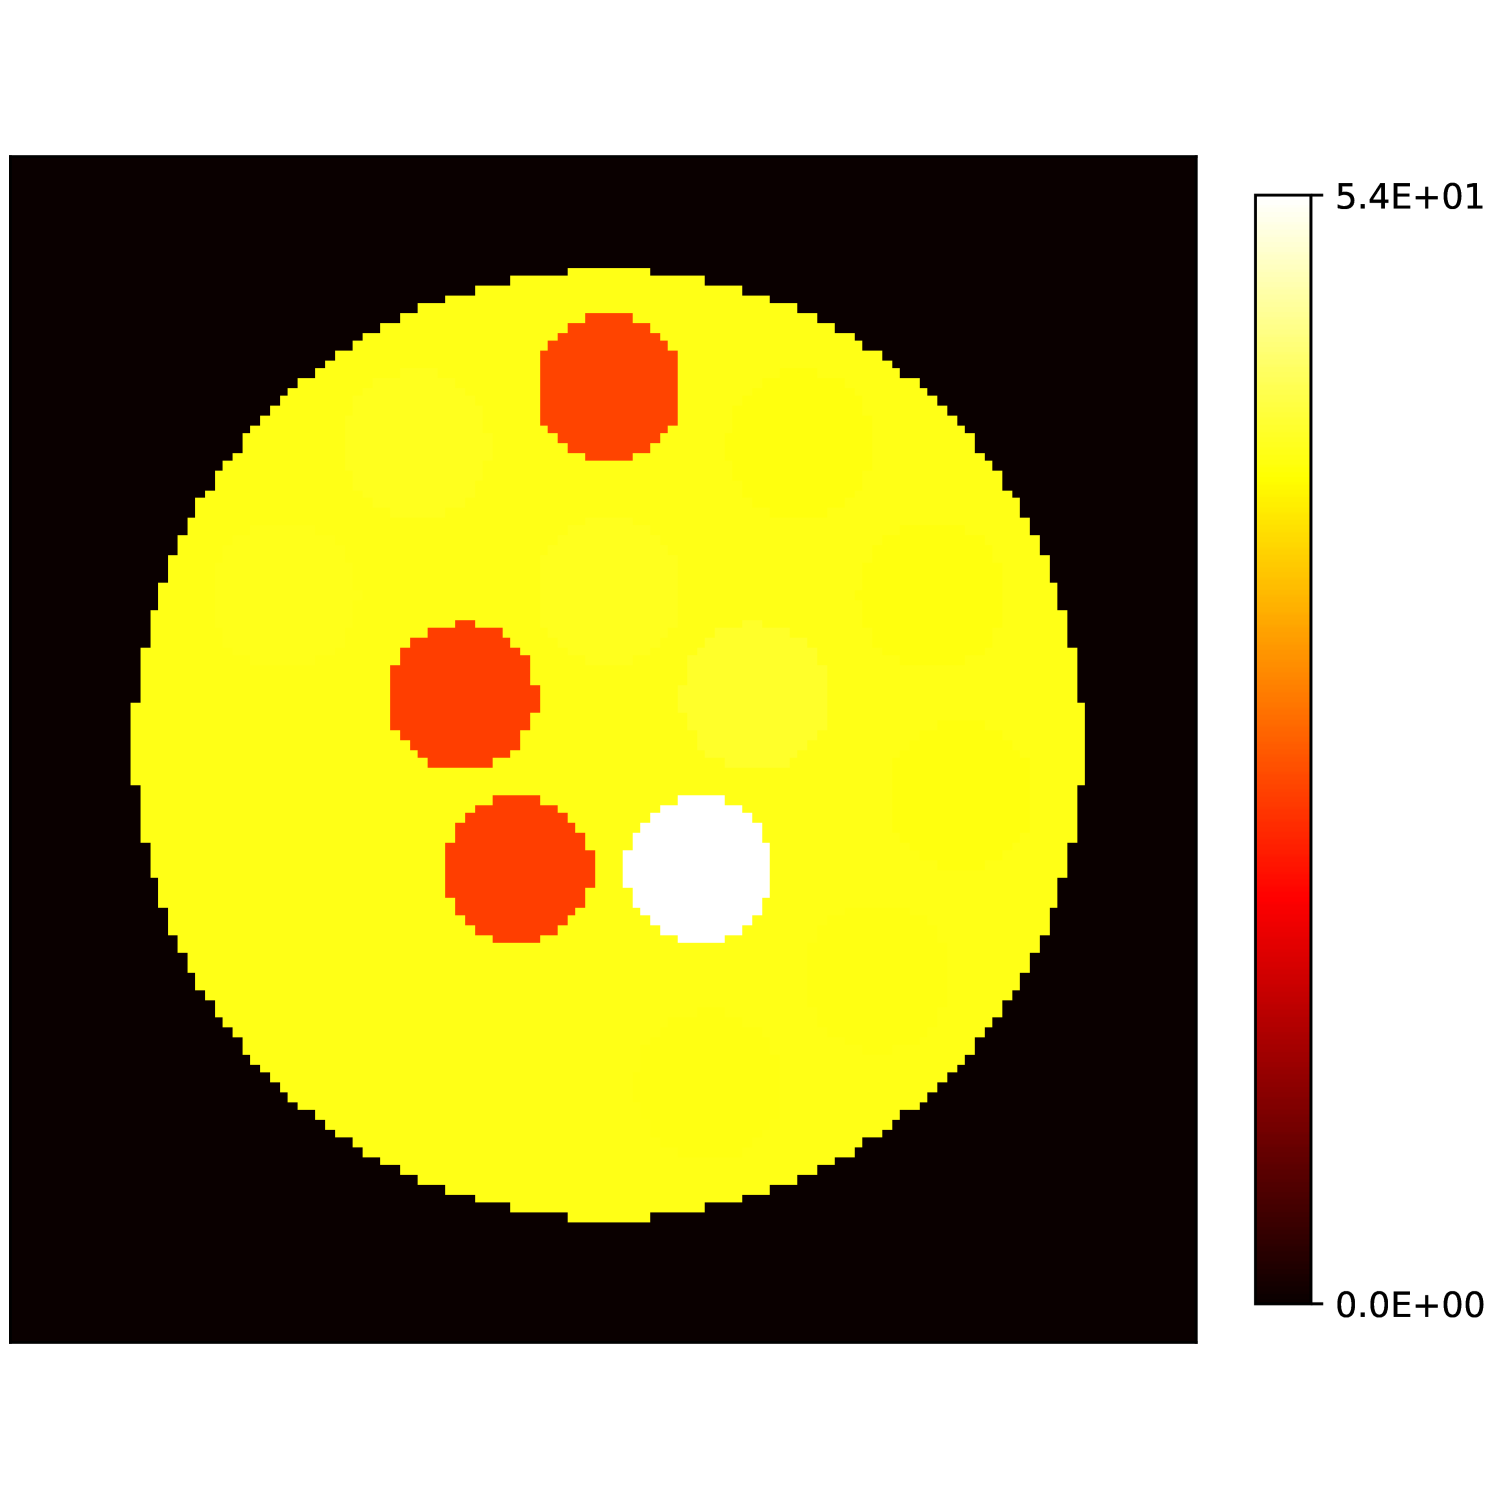

Our theoretical results show that generic concentrations and maps can be recovered exactly even when the fieldmap is not identifiable. To illustrate the impact of this fact, we perform a recovery experiment on a water (Fig. 2(a)), fat (Fig. 2(b)) and silicone (Fig. 2(c)) in silico phantom. The concentrations are all real. The values for the fieldmap and used to generate the signal are shown in Figs. 2(d) and 2(e). The echo times have the form where ms and ms with .

We solve (23) using projected gradient descent as initial iterate a vector with all components equal to one. Forward finite-differences were used to compute the gradient. The bound on the norm of the gradient is Hz at voxels with non-zero signal magnitude, and kHz at voxels with zero signal magnitude. This avoids imposing artificial constraints at voxels with no signal. The step size used is and the termination conditions

In Figs. 2(f), 2(g) and 2(h) show the recovered concentrations of water, fat and silicone, and Fig. 2(j) shows the recovered . These recovered quantities are all qualitatively similar to their true values. In contrast, Fig. 2(i) shows the recovered fieldmap, which differs from its true value. By comparing the errors in the recovered concentrations, we see that they are within a reasonable accuracy except in regions with a large magnitude for the fieldmap gradient, indicating a bound that is too small (Figs. 2(k), 2(l) and 2(m)). A similar behavior is seen in the recovered (Fig. 2(o)). The error for the recovered fieldmap tends to be larger outside the area of the phantom (Fig. 2(n)).